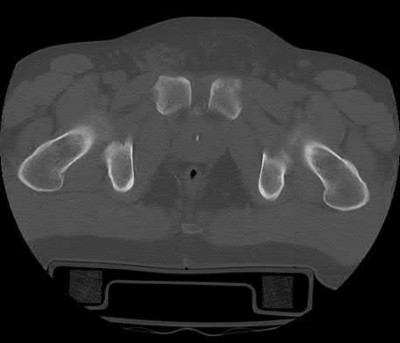

Which of the following images shows an injury pattern most consistent with a lateral compression type 3 pelvic ring injury?

Figure C is an axial CT scan of a lateral compression type 3 (LC3) pelvic ring injury.

Classically, LC3 injuries demonstrate an ipsilateral lateral compression and a contralateral APC (windswept pelvis) fracture pattern. The most common mechanism of injury in these cases is a rollover MVC or pedestrian vs. auto. LC1 injuries are characterized by an oblique or transverse ramus fracture and ipsilateral anterior sacral ala compression fracture, while LC2 injuries consist of a rami fracture and ipsilateral posterior ilium fracture dislocation (crescent fracture). While LC1 injuries can often initially be managed conservatively with protected weight-bearing and close observation, LC2 and LC3 pelvic ring injuries are almost universally operative.

Pennal et al. discuss a radiologic technique for assessing the forces producing pelvic disruption and its use in logically classifying pelvic injury. Based on this radiologic assessment and along with some biomechanical studies, they propose a classification system involving three major forces producing injury that can also be helpful in the management of these patients.

Young et al. performed a retrospective analysis of the plain radiographs of 142 cases of pelvic fractures and identified four patterns of force that presented with distinctive, recognizable radiographic appearances. They describe a classification system for pelvic fractures based on radiographic and clinical findings that correlates with associated injury to soft-tissue structures and enables the surgeon to begin corrective procedures rapidly.

Incorrect Answers:

Answer 1: This represents a lateral compression type 2 injury. Answer 2: This represents a lateral compression type 1 injury.

Answer 4: This represents an anterior posterior compression type 2 injury. Answer 5: This represents an anterior posterior compression type 3 injury.